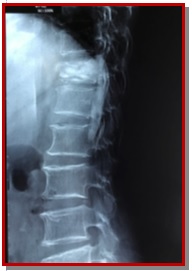

The aim of this study is to evaluate balloon kyphoplasty as a surgical option for osteoporotic thoracolumbar compression fracture. The study was conducted on 30 patients from January 2014 to December 2017. The anterior vertebral height, kyphotic angle and functional evaluation by Oswestry disability index (ODI) and visual analogue scale (VAS) score were recorded preoperatively, immediate post-operatively at 3, 6, 12 months and yearly then on. All patients showed improvement in mean kyphotic angle from 16.4 ± 3.5 to 5.6 ± 1.7 post-operatively and 8.4 ± 1.6 at final follow-up. There was significant increase in mean anterior vertebral height from 51 ± 7.3% before surgery to 75.5 ± 7.4% at one day after surgery and 71.2 ± 3.2% at the last follow-up. There was significant improvement in mean VAS score from 8.1 ± 0.9 before surgery to 2.2 ± 0.4 at one day, and 2.4 ± 0.3 at final follow-up. The improvement in patients’ ODI score after surgery from 71.4 ± 3.4 to 26.0 ± 4.8 at one day and 21.2 ± 5.5 at final follow-up was noted. The mean operating time was 45.5 ± 15.5 min for each vertebra. Within first day of surgery improvement in pain relief and mobility was experienced by all patients. The orthopedic balloon ruptured in one patient and it was replaced then procedure was continued with no complications. There were no neurological complications in all cases and there was no infections and any occurrence of symptomatic pulmonary embolism. In conclusion, balloon kyphoplasty is a good minimally invasive procedure where along with reduction of pain and disability there is also restoration of sagittal alignment post-operatively.